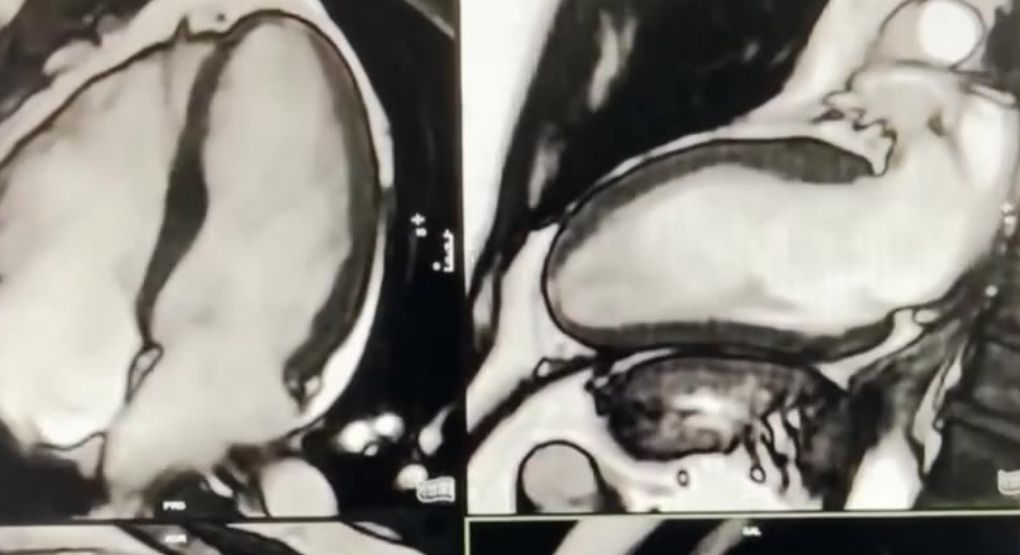

Exámenes como ecocardiogramas, tac o resonancia son claves para diagnósticos: Descubra los cuidados previos

El doctor Diego Ávila Sánchez, cardiólogo especialista en imágenes, explica cómo prepararse para cada prueba. Publicado en Repretel .